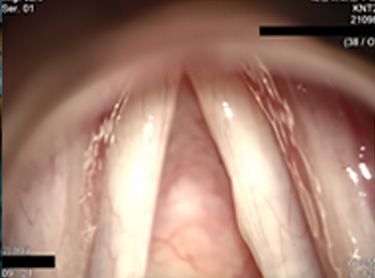

Pre-op vocal folds

1 year post-op vocal folds